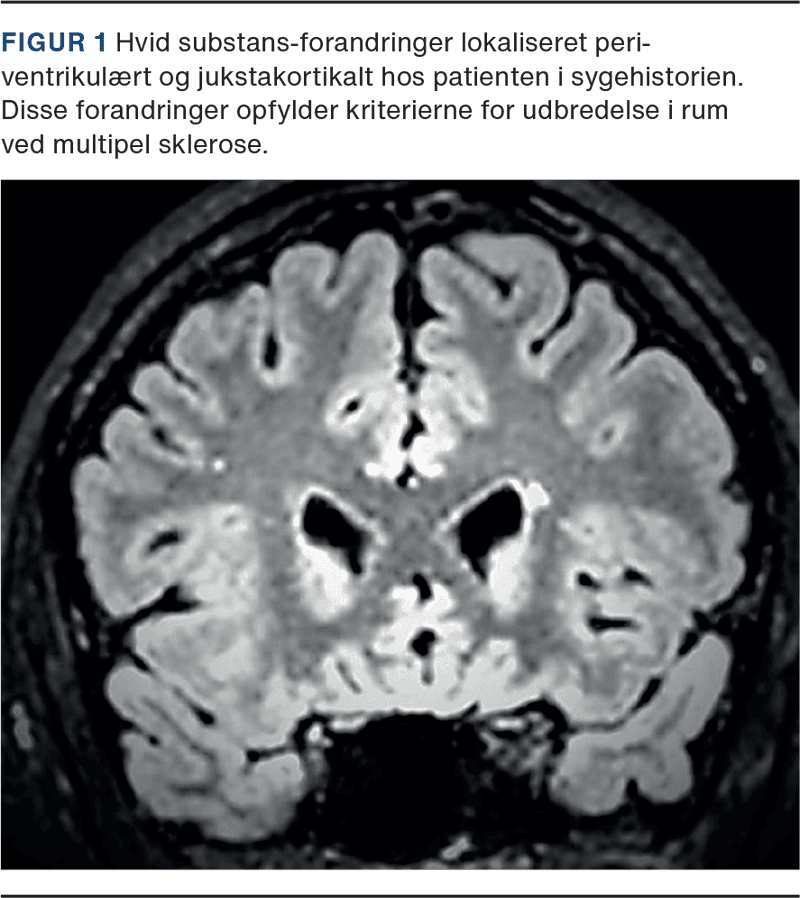

En 27-årig mand, tidligere rask, blev henvist i november 2021 på grund af tiltagende hovedpine. Han relaterede hovedpinen til et mindre hovedtraume under boldspil i juli 2021. Ved anamneseoptagelsen fremgik det dog, at hovedpinen opstod en uge efter hovedtraumet, som ikke var forbundet med bevidsthedspåvirkning. Samtidig kom det frem, at patienten havde deltaget i et overlevelseskursus en måned før, men han huskede ikke at have observeret hudforandringer. Han oplevede dobbeltsyn ved blik ligefrem, havde intermitterende svimmelhed, vedvarende lysfølsomhed og paræstesier i fingrene samt generelt nedsat energiniveau. Undersøgelserne viste latent udadskelen og indskrænket indaddrejning af øjnene. MR-skanning af cerebrum i april 2022 viste jukstakortikale og periventrikulære læsioner (Figur 1).

På mistanke om MS blev der foretaget spinalvæskeundersøgelse i maj 2022, som viste otte mononukleære celler, forhøjet IgG-indeks og oligoklonale bånd. Endelig fandtes positivt, intratekalt Borrelia-antistofindeks. Patienten startede behandling med doxycyclin 200 mg dagligt i tre uger. Ved opfølgning efter 12 måneder anførte han betydelig bedring af hovedpinen og tydelig mindskning af lysoverfølsomheden, men fortsat påvirkning af livskvaliteten, da han ofte måtte selektere i, hvad han kunne overkomme. Hukommelsen var god, men der var fortsat koncentrationsbesvær. Øjenlægeundersøgelse i juni 2023 viste helt normale forhold. Kontrol-MR-skanninger viste uændrede forhold i september 2022 og i september 2023.